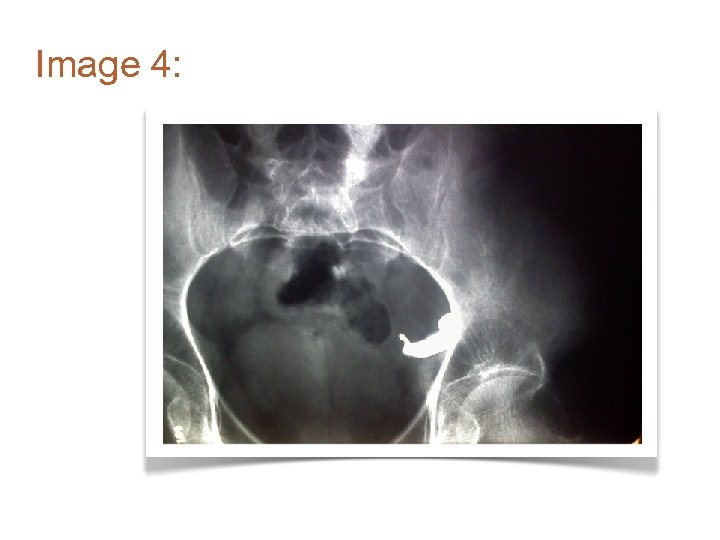

Image 4: